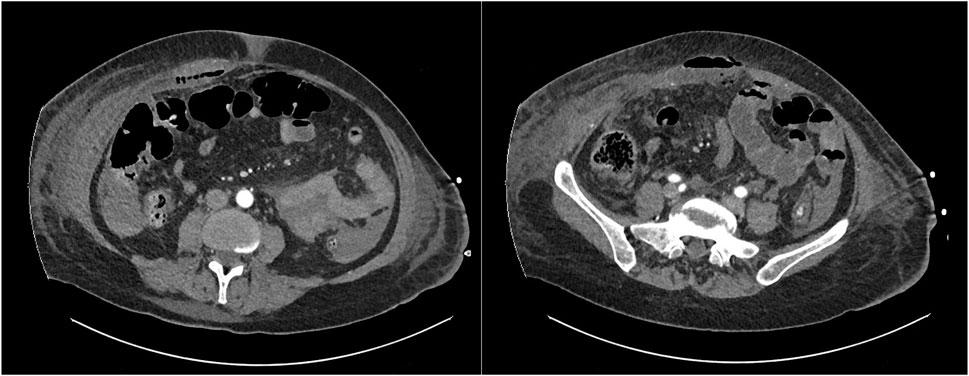

入院后第10天,出现右腹部发热和肿胀。右腹部触诊时出现疼痛和腹部防护。血液检查显示急性期反应物,CT显示存在局部气腹,右侧肌后(直肠后)间隙有广泛的脓肿,达到肋骨水平,腹膜前受累,所有这些都与延迟空肠穿孔和肌后间隙瘘口有关(图1)。

图1 脓肿通过右直肠后间隙延伸,并伴有局部气腹